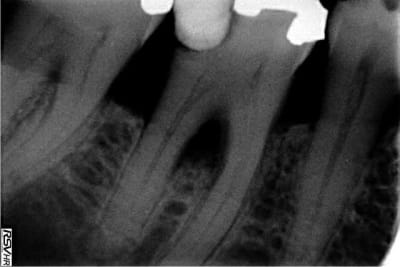

Bonjour, y 'aurait t'il quelqu'un qui pourrait m'aiguiller sur la complication que j'ai eue pendant une anesthésie intra osseuse sur une 46 radio ci jointe.

je me suis mis en distal de 46, avec QS4 et aiguille ostéocentrale je fais une penetration intra osseuse sans grande difficulté. J'injecte un tiers de l'aiguille en vitesse lente et là patiente m'a fait des signes comme quoi elle avait une douleur importante dans la zone postérieure à cette anesthésie en se tenant la joue jusqu' à l'oreille.

Il faudrait une pano; tu as peut être un kyste qui est sorti de sa torpeur lors de son effraction par le liquide qui se diffuse dans la corticale.

quant'à ton probleme nickle c'est peut etre la pression du liquide anesthesique sur l'inflammation peri apicale existante qui a produit cette douleur ;dans un cas comme celui ci tu arretes l'injection quelques secondes et tu repends ;donc en vitesse tres lente